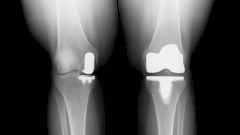

Когда артроз колена не остановить, поможет ли эндопротез?

Процедура представляет собой полную или частичную замену коленного сустава и заключается в том, чтобы установить протез вместо верхней части большой берцовой кости и нижней части бедренной кости. При этом в зависимости от особенностей работы для каждого из участков используются различные материалы. Протезы изготавливают из керамики, сплавов металлов или пластика. Часть, которая заменяет коленную чашечку, выполняется из пластика, деталь, прилегающая к бедренной кости, — из биосовместимого сплава, а со сторон большой берцовой кости — из комбинации пластика и металла.

Замену коленного сустава проводят при выраженных поражениях в костно-хрящевой ткани, данная процедура не имеет срочных показаний и всегда проводится в плановом порядке — например, при развитом артрозе коленного сустава, ревматоидных артритах. Операция по замене коленного сустава осуществляется под общей или эпидуральной (местной) анестезией.